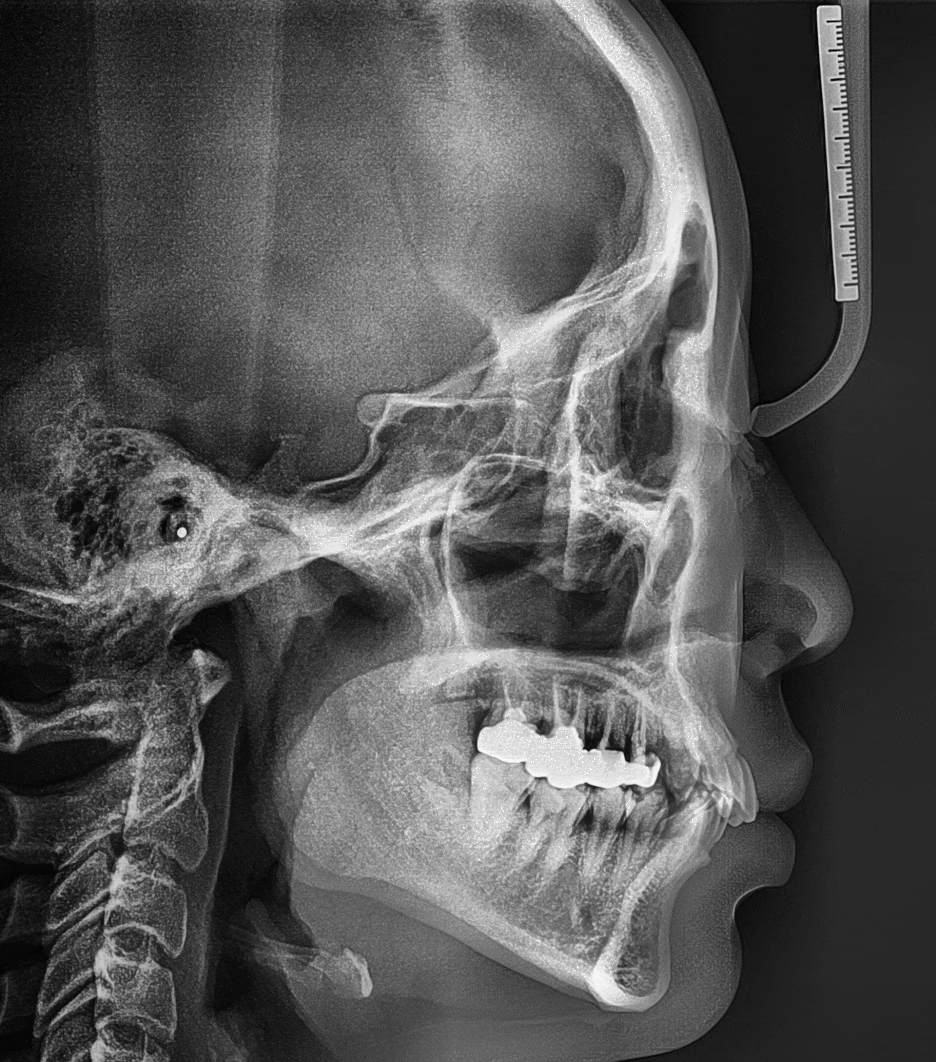

1. 치관 파절, 뿌리 끝 염증(Apical lesion) 발견

2. 잔존치근 발거

3. 발치와보존술 시행

4. 발치와보존술 후, 고정체 식립 및

인비절라인 치아교정 치료 시작

- 치아의 총생 및 과개교합 이 원인